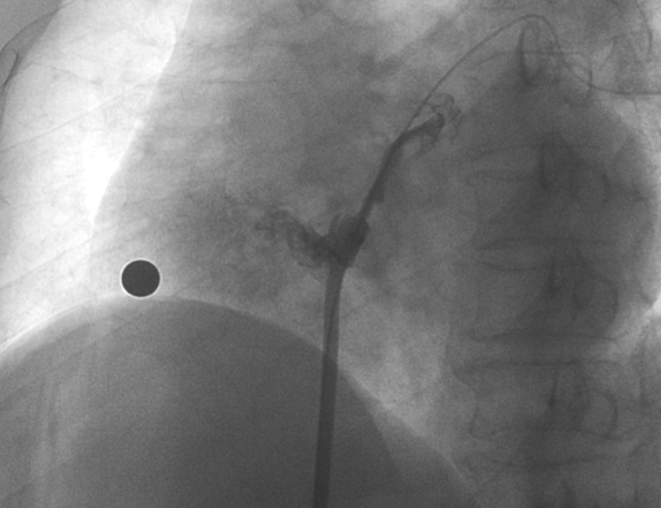

造影顯示長隧道型PFO

術中造影顯示患者為PFO且長隧道型,目前市場上已商業化的PFO封堵器難以滿足該患者解剖結構封堵需求。迪創醫療自主研發的OmniSeal PFO封堵器自適應性雙盤貼合設計能廣泛適應不同PFO隧道長度的解剖結構和形態,其雙盤外包覆式阻流和隧道內填充阻流相結合的雙重阻流設計,可為此患者實現有效封堵。與此同時,OmniSeal首創的完全可穿刺式設計,也為此患者最大程度地保留了房間隔區域穿刺通道,以實現全兼容未來可能的左心系統二次介入術。術終造影和心臟超聲顯示封堵完全、效果良好。作為OmniSeal的首例臨床應用,本次手術的順利完成和優異效果充分體現了產品的設計創新優勢。